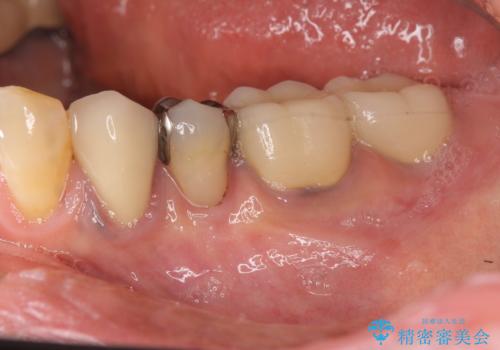

[遊離歯肉移植] インプラント周囲の角化歯肉の獲得

![[遊離歯肉移植] インプラント周囲の角化歯肉の獲得の症例 治療前](https://seimitsushinbi.jp/wp/wp-content/uploads/2020/01/ed937e86f21629e18e8c1dc62b85d1a9-500x350.jpg?v=1580303875)